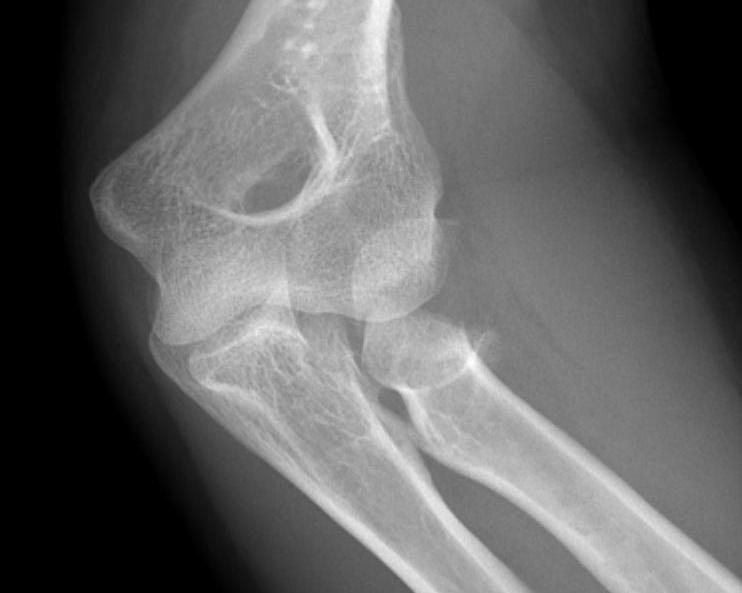

Hotchkiss modification of Mason Classification

Type 1: Undisplaced fracture / Intra-articular displacement < 2mm/ No mechanical limitation to forearm rotation

If in doubt, inject LA into radiocapitellar joint / soft spot and rotate elbow

Type I radial head fractures